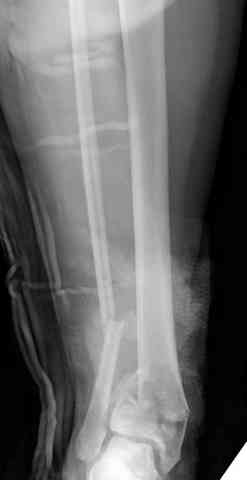

Первичная пластина или интрамедуллярный фиксатор на малоберцовую зависит от характера перелома, косые и многооскольчатые пластинами, а поперечных можно интрамедуллярными фиксаторами. Восстановленная длина малоберцовой служит ориентиром и помогает определению высоты большеберцовой во время восстановления.

Переломы пилона сопровождаются ударом со сминанием в метафизарной части большеберцовой, то есть со значительной потерей костного объема.

При репозиции суставных поверхностей образуются полости в метафизарных отделах, без заполнения их

структуральными элементами невозможно предохраниться от посттравматической деформации. Латеральная колонна удерживается малоберцовой поэтому голень деформируется в варус.

Здесь выставлена пара случаев перелома пилона, оба

случая леченные этапным наружным фиксатором.

Второй случай фиксирован аппаратом Илизарова.